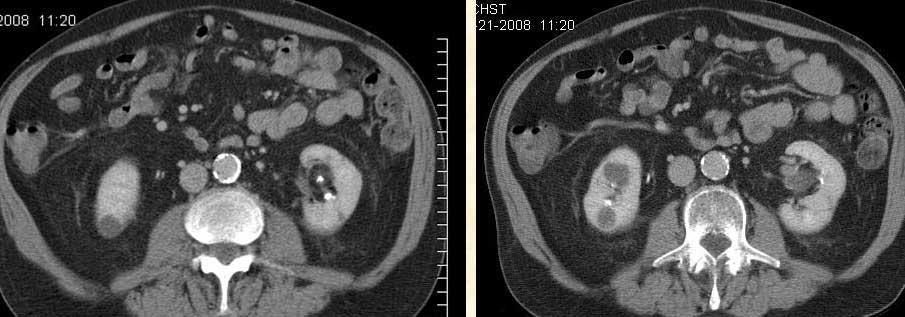

CT-scan dada pada 21 Juni 2008

1.      Terdapat massa sebesar 2,7 cm pada daerah hilus kanan yang dicurigai malignansi (proses keganasan).

2.      Kemungkinan post-obstruktif pneumonitis pada lobus tengah paru kanan.

3.      Terdapat massa baru sebesar 2,7 cm pada adrenal sesuai dengan metastasis.

4.      Fibrosis yang menetap ada apeks (ujung atas) paru.